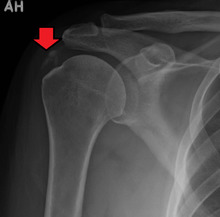

An x-ray showing calcific deposits in the area of the tendons of the rotator cuff muscles

The calcific deposits are visible on X-ray as discrete lumps or cloudy areas. The deposits look cloudy on X-ray if they are in the process of reabsorption, and this is also when they cause the most pain. The deposits are crystalline when in their resting phase and like toothpaste in the reabsorptive phase. However, poor correlation exists between the appearance of a calcific deposit on plain X-rays and its consistency on needling. Ultrasound is also useful to depict calcific deposits and closely correlates with the stage of disease.[6]